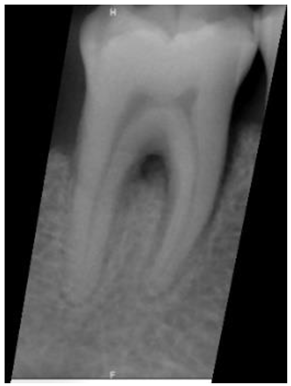

| Original Images | Gaussian High-Pass Filter | Gaussian High-Pass Filter + Mask | |

|---|---|---|---|

| Validation Accuracy | 84.16% | 87.21% | 94.97% |

| Validation Loss | 0.7634 | 0.4578 | 0.1822 |

| Image | ![]() | ![]() | ![]() |